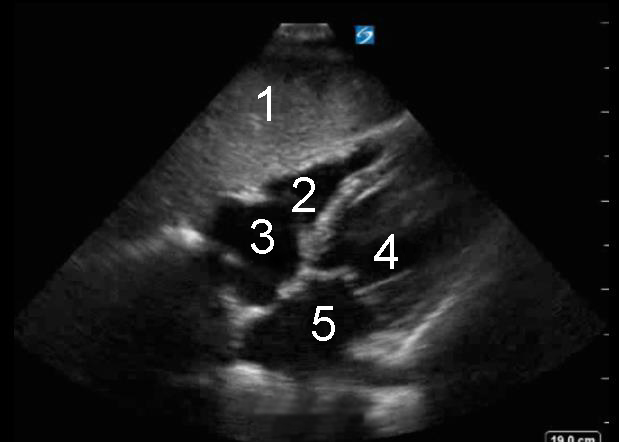

Image : Cœur, vue sous-xiphoïdienne

1. Foie

2. Ventricule droit (VD)

3. Oreillette droite (RA)

4. Ventricule gauche (VG)

5. • Oreillette gauche (OG)